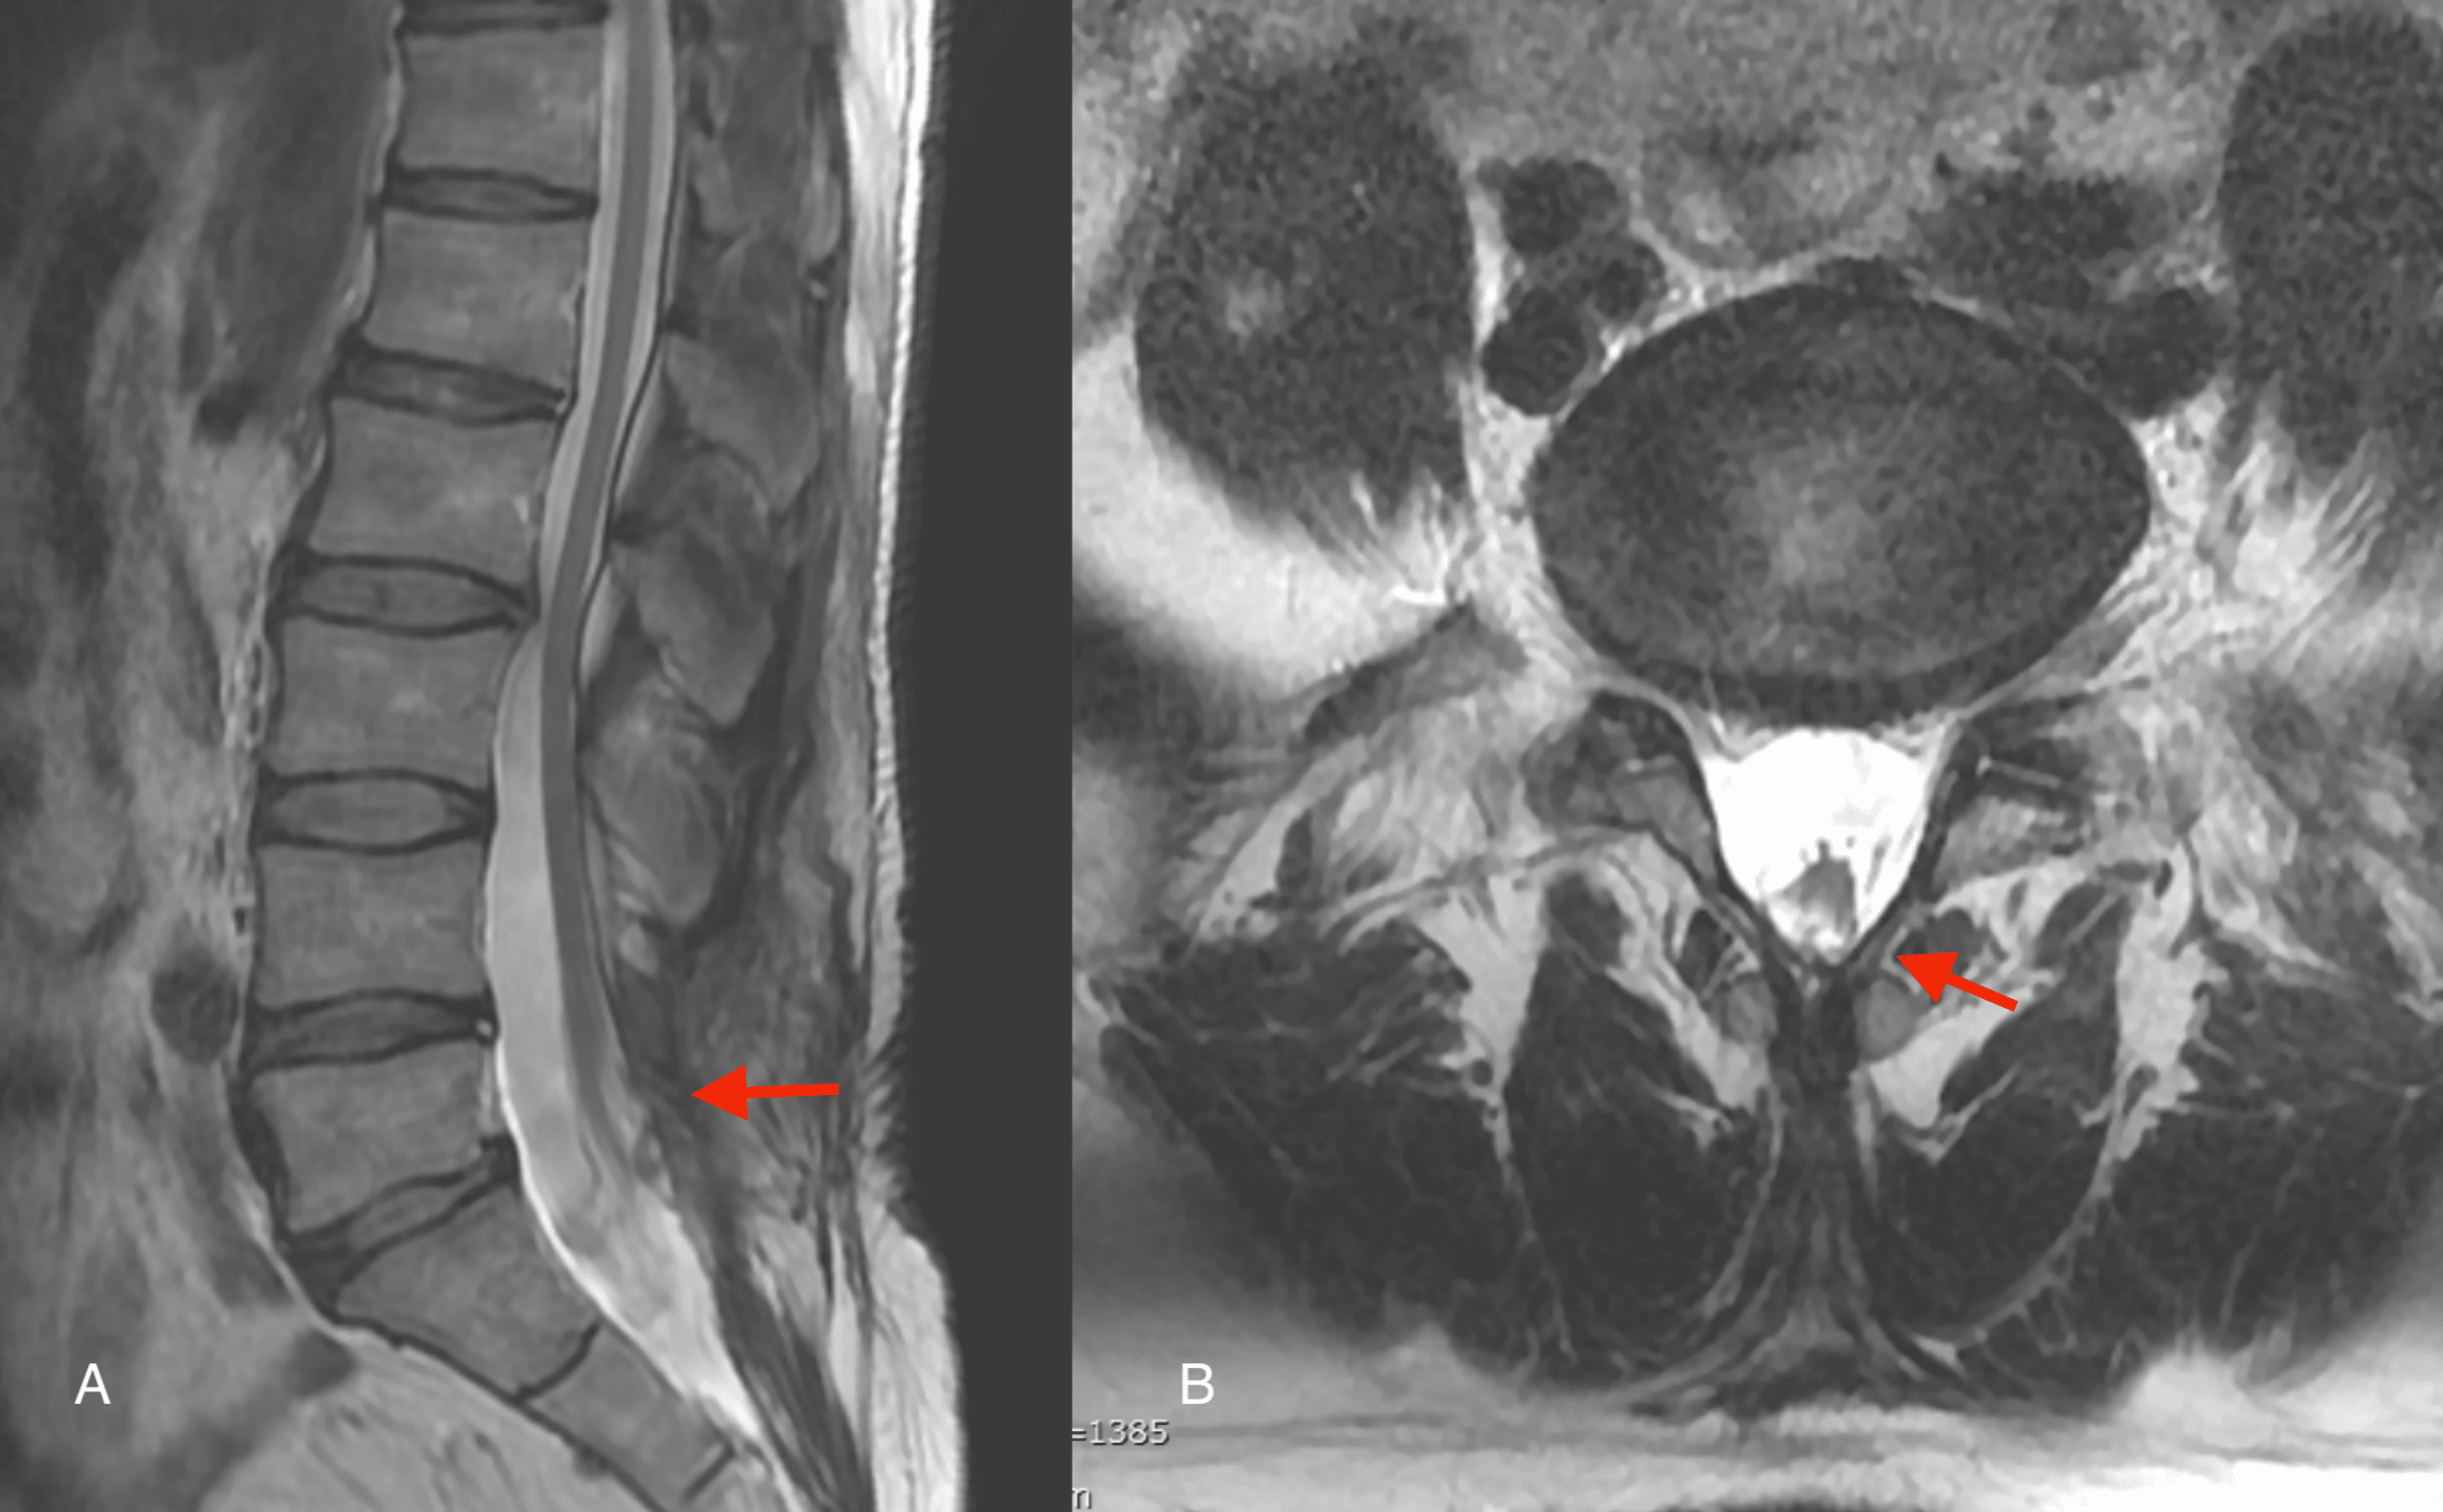

Percutaneous endoscopic interlaminar discectomy. A) Lateral radioscopic Endoscopic Discectomy In Delhi discover the microscopic endoscopic disc surgery hospital in delhi. endoscopic discectomy is a minimally invasive surgical treatment that is used to remove herniated disc material that is. Explore advanced endoscopic procedures and expert care. endoscopic discectomy is a minimally invasive spine surgery technique that utilizes an endoscope to treat herniated,. endoscopic spine surgeries can be used. Endoscopic Discectomy In Delhi.